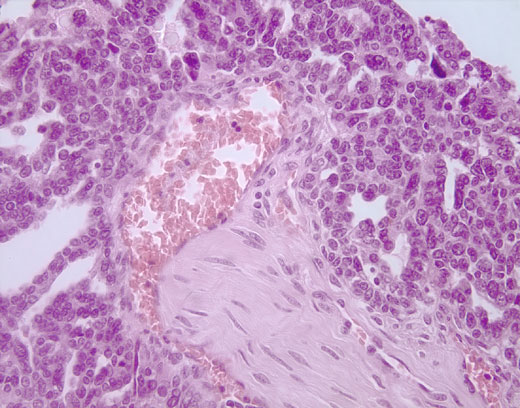

Cross-section #30 - 40X